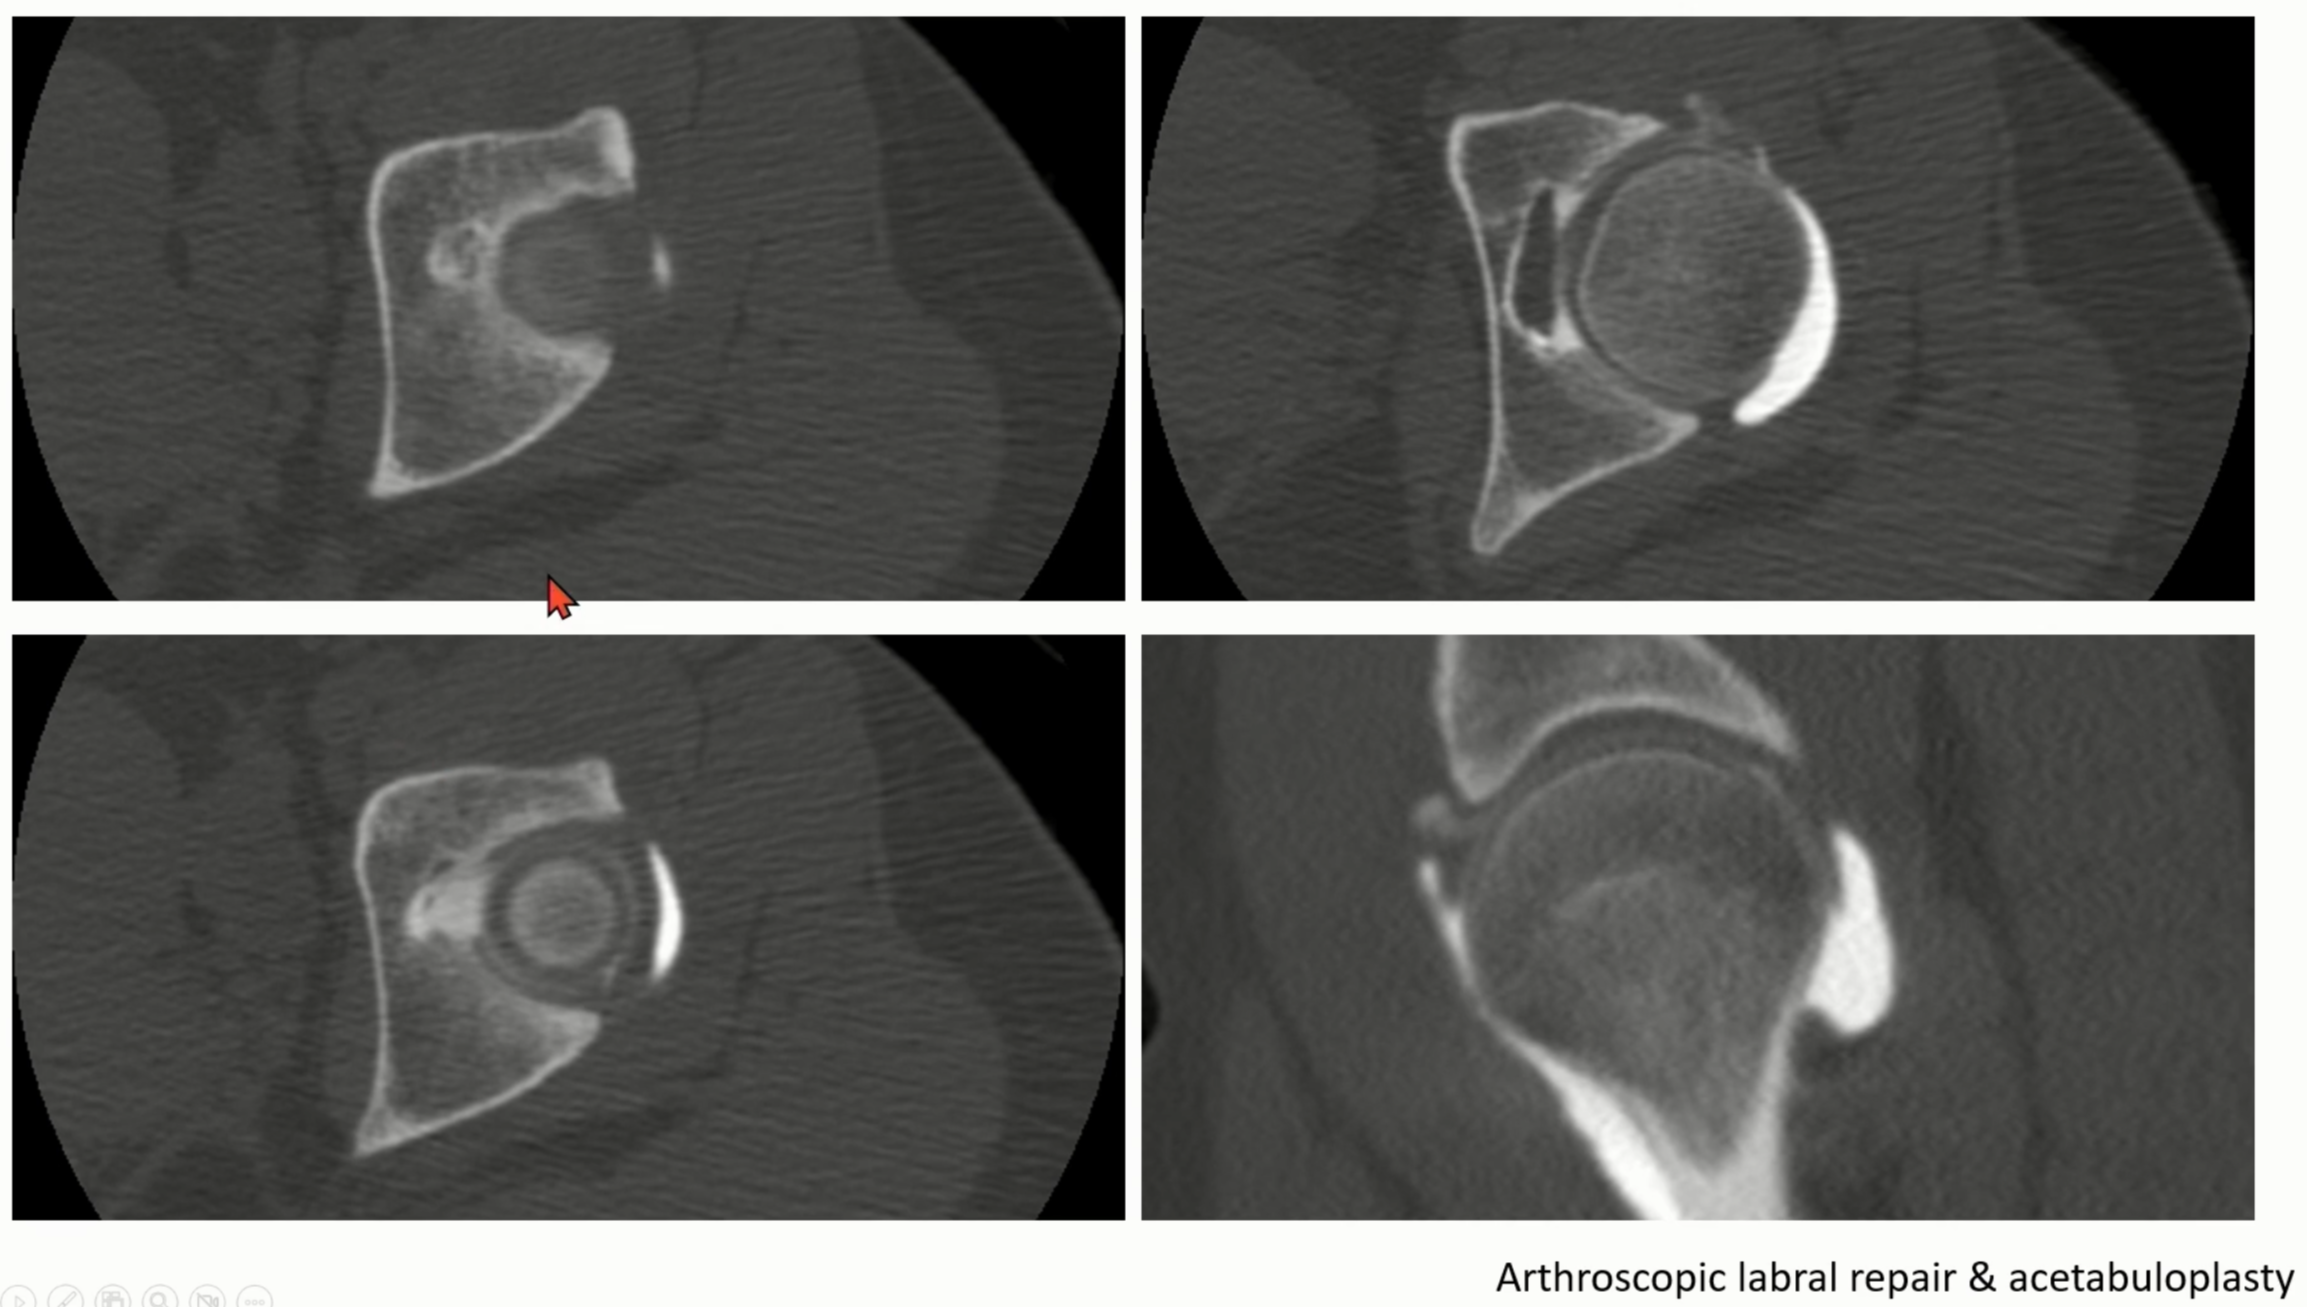

CT나 MRI에서는 더 확실하게 볼 수 있습니다.

head/neck junction 부위에 cyst나 bump가 보이며, head의 구형이 소실된 모습을 볼 수 있습니다.

CT나 MRI상에서는 앞에서 언급했던, retroversion의 이상을 쉽게 측정할 수 있습니다.

Labrum의 이상이나 Chondral 이상 같이 동반된 병변을 찾을 수 있습니다

Case 2)